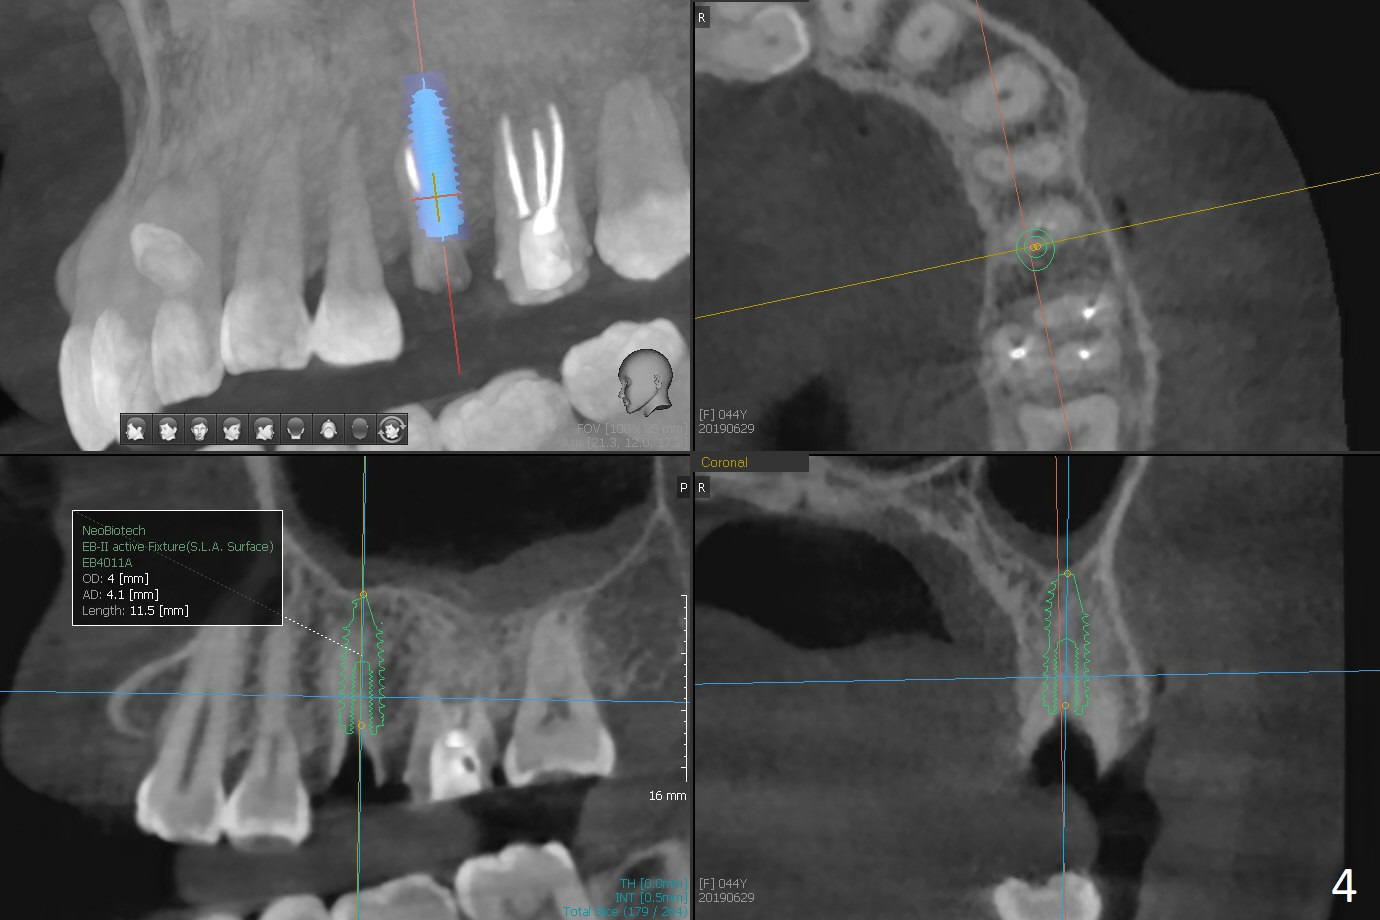

A 44-year-old woman used to have splinted crowns at #13 and 14 (Fig.1). Their dislodgement is due to residual roots at #13 and distal caries at #14 (Fig.2 ^). To avoid the distally curved apex of #12 and to have ideal trajectory of an IBS implant (Fig.4), osteotomy will be initiated in the distopalatal slope of the socket (Fig.3 arrowheads). The patient wants to correct the tooth #8 with rotation (Fig.5), which is due to a mesiodens (Fig.1,2 M). It will be accessed palatal (Fig.5 P). In fact there is percussion at #14 associated with MB2 (Fig.6 arrowheads) and PARL (*).